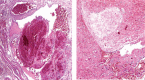

Outcomes: The mass was excised completely, and the histopathology examination confirmed the diagnosis of cavernous hemangioma with prominent formation of phleboliths. The patient recovered very well without dysfunctions.